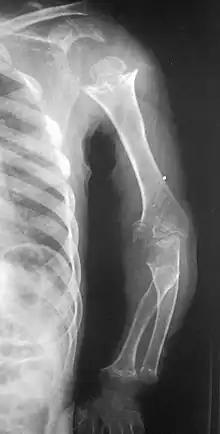

Pseudoachondroplasia. Shoulders and Humeri. Note the dysplastic proximal humeral epiphyses, metaphyseal broadening, irregularity and metaphyseal line of ossification. These changes are collectively known as "rachitic-like changes". Lesions are bilateral and symmetrical.

• Dysplastic/hypoplastic epiphyses especially of shoulders and around the knees.

• Metaphyseal broadening, irregularity and metaphyseal line of ossification. These abnormalities that are typically encountered in proximal humerus and around the knees are collectively known as “rachitic-like changes”.

• Radiographic lesions of the appendicular skeleton are typically bilateral and symmetric.